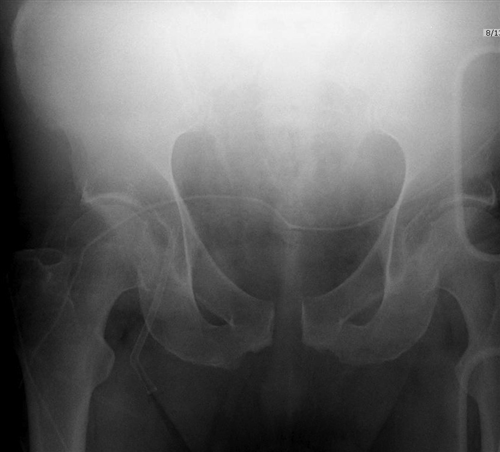

APC (AP compression)는 anterior injury로 symphysis diasthesis가 특징적입니다.

APC I : symphysis가 약간 열리고(2.5cm까지 경과관찰가능) SI jt가 정상 혹은 앞으로 약간 나오기도 합니다.